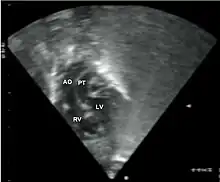

•Echocardiogram: An echocardiogram is an ultrasound of the heart that accurately assesses the heart’s structure and function, and can show the specific features of TGA, if present. This imaging modality allows for the definitive diagnosis of TGA to be made.[3]

Abbreviations: LV and RV=left and right ventricle, PT=pulmonary trunk, VSD=ventricular septal defect, PS=pulmonary stenosis.